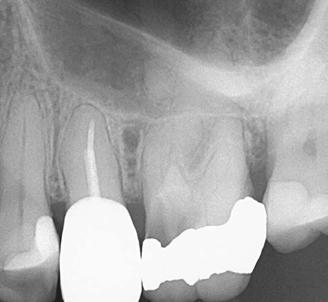

Clinical case performed by Dr. Brett Gilbert (Figures 4 and 5)

In this case, Dr. Gilbert was initially unable to locate the MB2 canal, despite thorough attempts using ultrasonic and a microscope. After performing the irrigation protocol with Odne®Clean, the MB2 became visible. Following activation, the filling material extended completely through the MB2.

Figures 4 and 5: Clinical case performed by Dr. Brett Gilbert